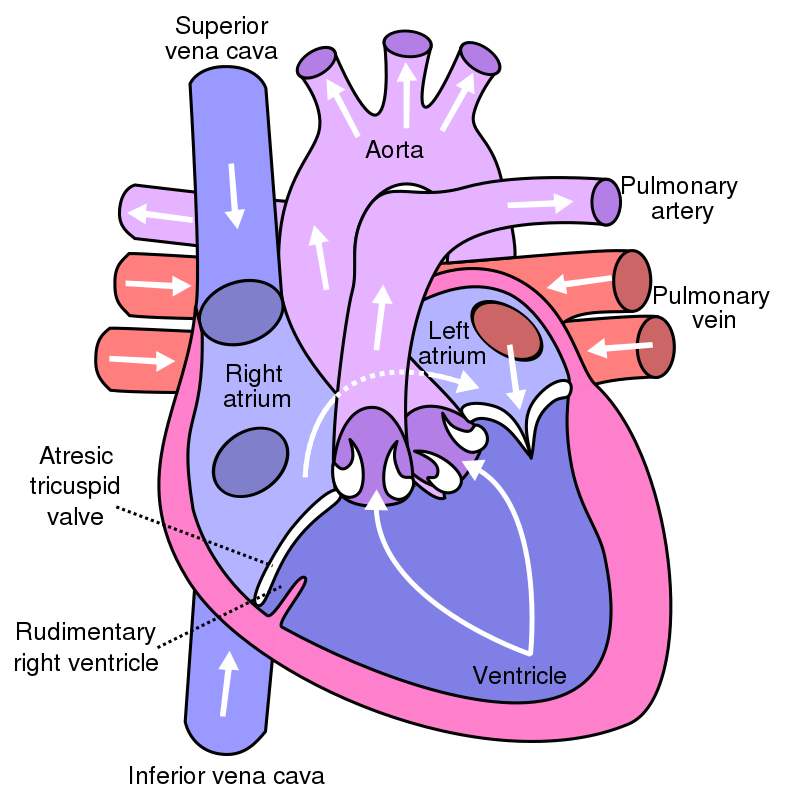

Tricuspid Atresia

Tricuspid atresia is due to failure of the orifice of the tricuspid valve to form.

In tricuspid atresia a hypoplastic right ventricle is present.

Tricuspid atresia frequently results in a right-to-left shunt and is linked to atrial septal defect.

Tricuspid atresia has an early cyanotic presentation.